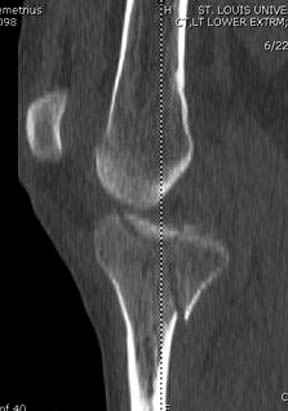

Здесь как раз тот случай, когда результат зависит не только от мастерства хирурга, но и от наличия современных методов исследования. Например, КТ которая поможет рассчитать направления шурупов и установку импланта. Кроме этого, поможет определиться с доступом.

На представленных предоперационных срезах КТ огромный задне-медиальный фрагмент расположен больше кзади, чем медиально. Для планирования, кроме поперечных срезов, надо ориентироваться на корональные срезы, которые укажут топографию верхушки медиального фрагмента.